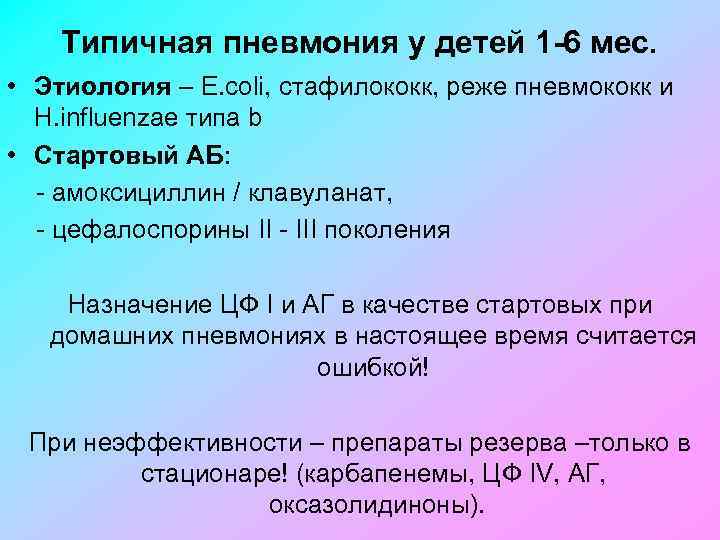

Острая внебольничная пневмония по МКБ-10: признаки и примеры